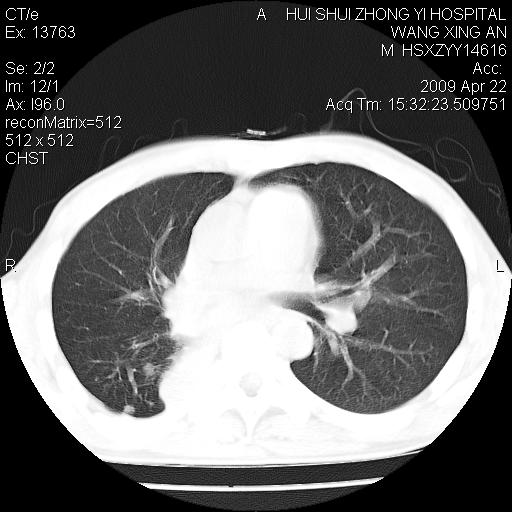

标题: CT19534:患者男、46岁咳嗽、胸痛半月。 [打印本页]

标题: CT19534:患者男、46岁咳嗽、胸痛半月。

1、右下肺中央型肺癌并右肺转移,右肺下叶不张。(右肺有结节影)。

2、右中上肺陈旧性肺结核(因为大多为纤维灶)。

右肺纤维灶

3、右中上肺陈旧性肺结核(右肺见纤维化病灶及点状钙化)。

1)右肺中间段支气管癌并右肺下叶肺不张。2)右肺上叶、两肺下叶背段感染性病变。3)右侧少量胸腔积液。